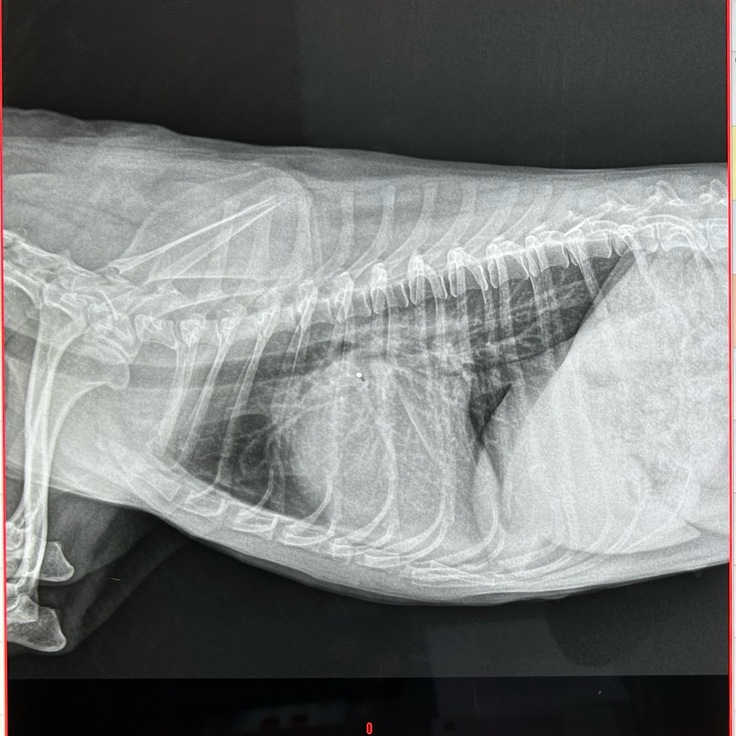

・今回のレントゲンです

心臓の形がはっきりとわからず、白くもやがかっています。

背骨側やお腹側へ広くくっつくように見えます。